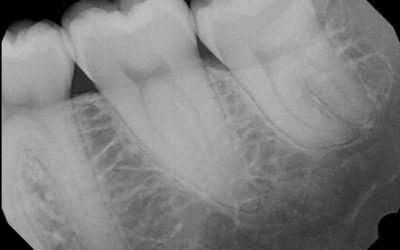

Dental X-Rays: Why Your Mouth Needs Them

One of the most common questions patients ask is “Do I NEED x-rays?” Radiation is a huge concern because of its correlation to cancer and other genetic diseases, so it is understandable that many patients would rather never get x-rays. However, x-rays are a critical...